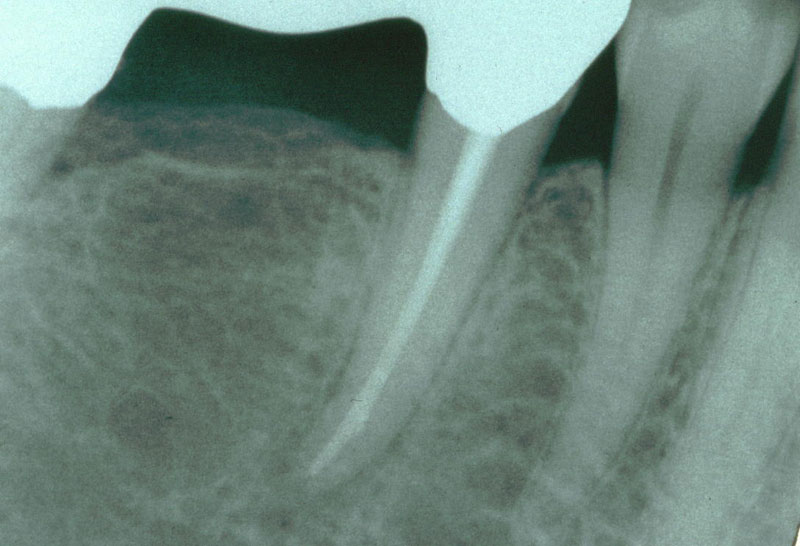

Wurzelrest nach Versuch der Kariesentfernung

Extraktionsgrund: kariöse Zerstörung des Zahnstumpfs nach unbemerkter

Abzementierung des Brückenankers

Röntgenbild unmittelbar vor Extraktion